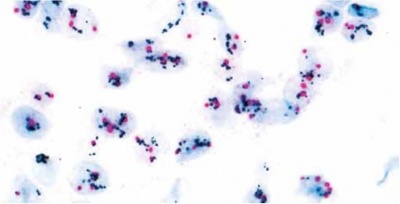

הגן HER2 מתגלה על ידי probe A צבוע עם DNP או dinitrophenyl ומשתקף בצבע שחור על ידי probe B שהוא SISH או silver ISH DNP. הצנטרומר של כרומוזום 17 נקשר על ידי probe A צבוע עם DIG או digoxigenin ומתגלה על ידי probe C Red ISH DIG. צביעה כפולה שניתנת להתבוננות במיקרוסקופ אור, בה הגן HER2 מופיעה כנקודות שחורות, וכרומוזום 17 נצבע אדום (ראו תמונה). בשיטה זו אין הצביעה דוהה לאורך זמן. הבדיקה ניתנת לביצוע בדגימות ביופסיה שקובעו ושומרו בשיטות שונות. הניסיון שהצטבר מראה ששיטה זו נותנת תוצאות אמינות יותר מאלה שהושגו בשיטת צביעה היסטוכימית, וכמו כן שיטה זו זולה יותר לביצוע ואינה מצריכה מיקרוסקופ פלואורסצנטי יקר שאינו זמין תמיד כמו זה הנדרש בבדיקת FISH-HER2.